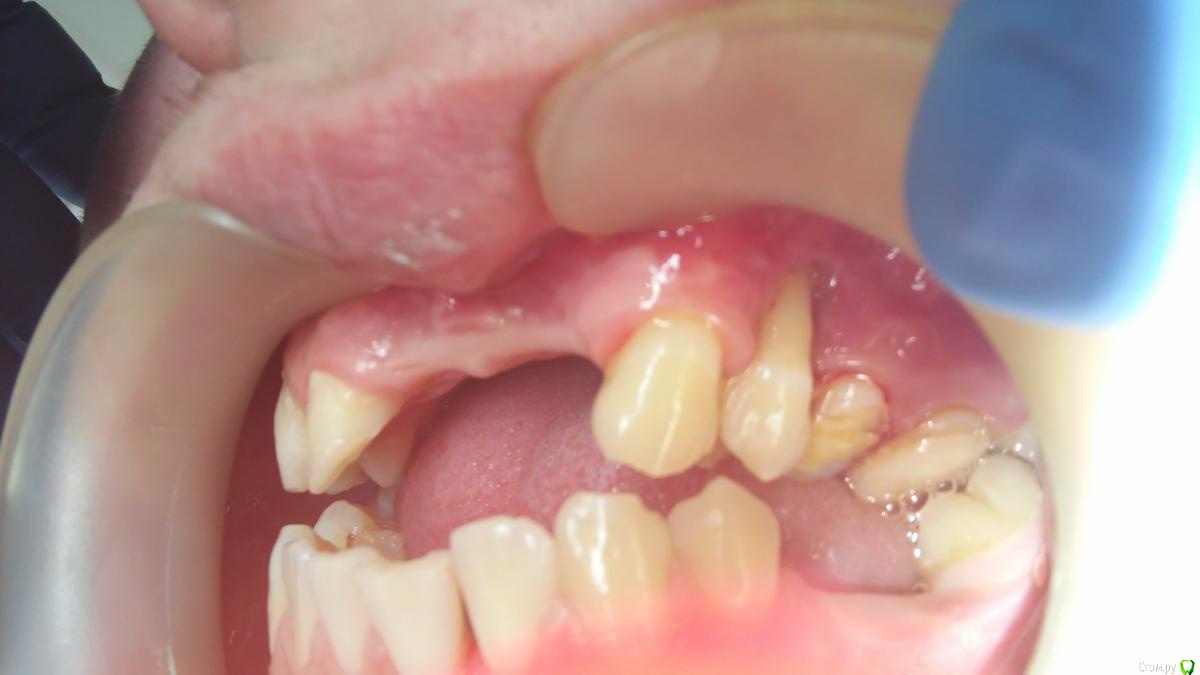

ANCHOUSE Опубликовано 21 апреля, 2015 Поделиться Опубликовано 21 апреля, 2015 (изменено) Пациент,19 лет,реабилитация после дтпНаправлен из стационара на ортодонтиюРецессии 31,32(подвижен 1ст.),2424,32 на удаление 100%? Изменено 21 апреля, 2015 пользователем ANCHOUSE Ссылка на комментарий

ANCHOUSE Опубликовано 21 апреля, 2015 Автор Поделиться Опубликовано 21 апреля, 2015 Парня сбил грузовик,последствия тяжелые,рецессии это уже лирика...... Насчет 32 сомнений нет,там потеря кости значительная,подвижность большая,а вот 24-пат.подв. нет,м\з перегородки сохранены.Еще очень плохая гигена,что усугубляет картину...Должет подойти на к/осм. после проф.гигиены со снимком... Ссылка на комментарий